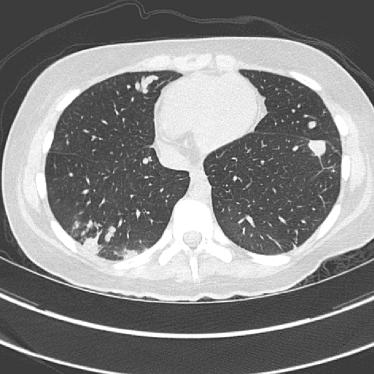

Refer to caption(a) Clinical Standard IRRefer to caption(a) Clinical Standard IR

Refer to caption(b) JENGRefer to caption(b) JENG

Refer to caption(c) Clinical Standard IRRefer to caption(c) Clinical Standard IR

Refer to caption(d) JENGRefer to caption(d) JENG

Figure 14: Qualitative clinical results from a thoracic CT staging dataset for a 12-year-old with osteosarcoma with pulmonary metastases. The clinical standard hybrid IR is shown on the left and JENG is on the right. (a) The clinical standard hybrid IR in lung window with a window center of -600 HU and a window width of 1500 HU. (b) JENG at a resolution comparable to the clinical standard, but with less noise and fewer artifacts. (c) The clinical standard hybrid IR in soft tissue window with a window center of 55 HU and a window width of 440 HU. A metastatic lung cancer nodule can be found in the left upper lobe. (d) JENG in soft tissue window at a comparable resolution, but with less noise and fewer artifacts. Note that JENG is not fully corrected for beam hardening artifacts.